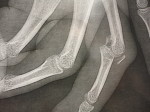

Fractures des métacarpiens et des phalanges

Les fractures des os de la main (métacarpiens et phalanges) présentent un éventail multiple de traitement.

Les traitements varient en fonction de la localisation et du type de fractures.